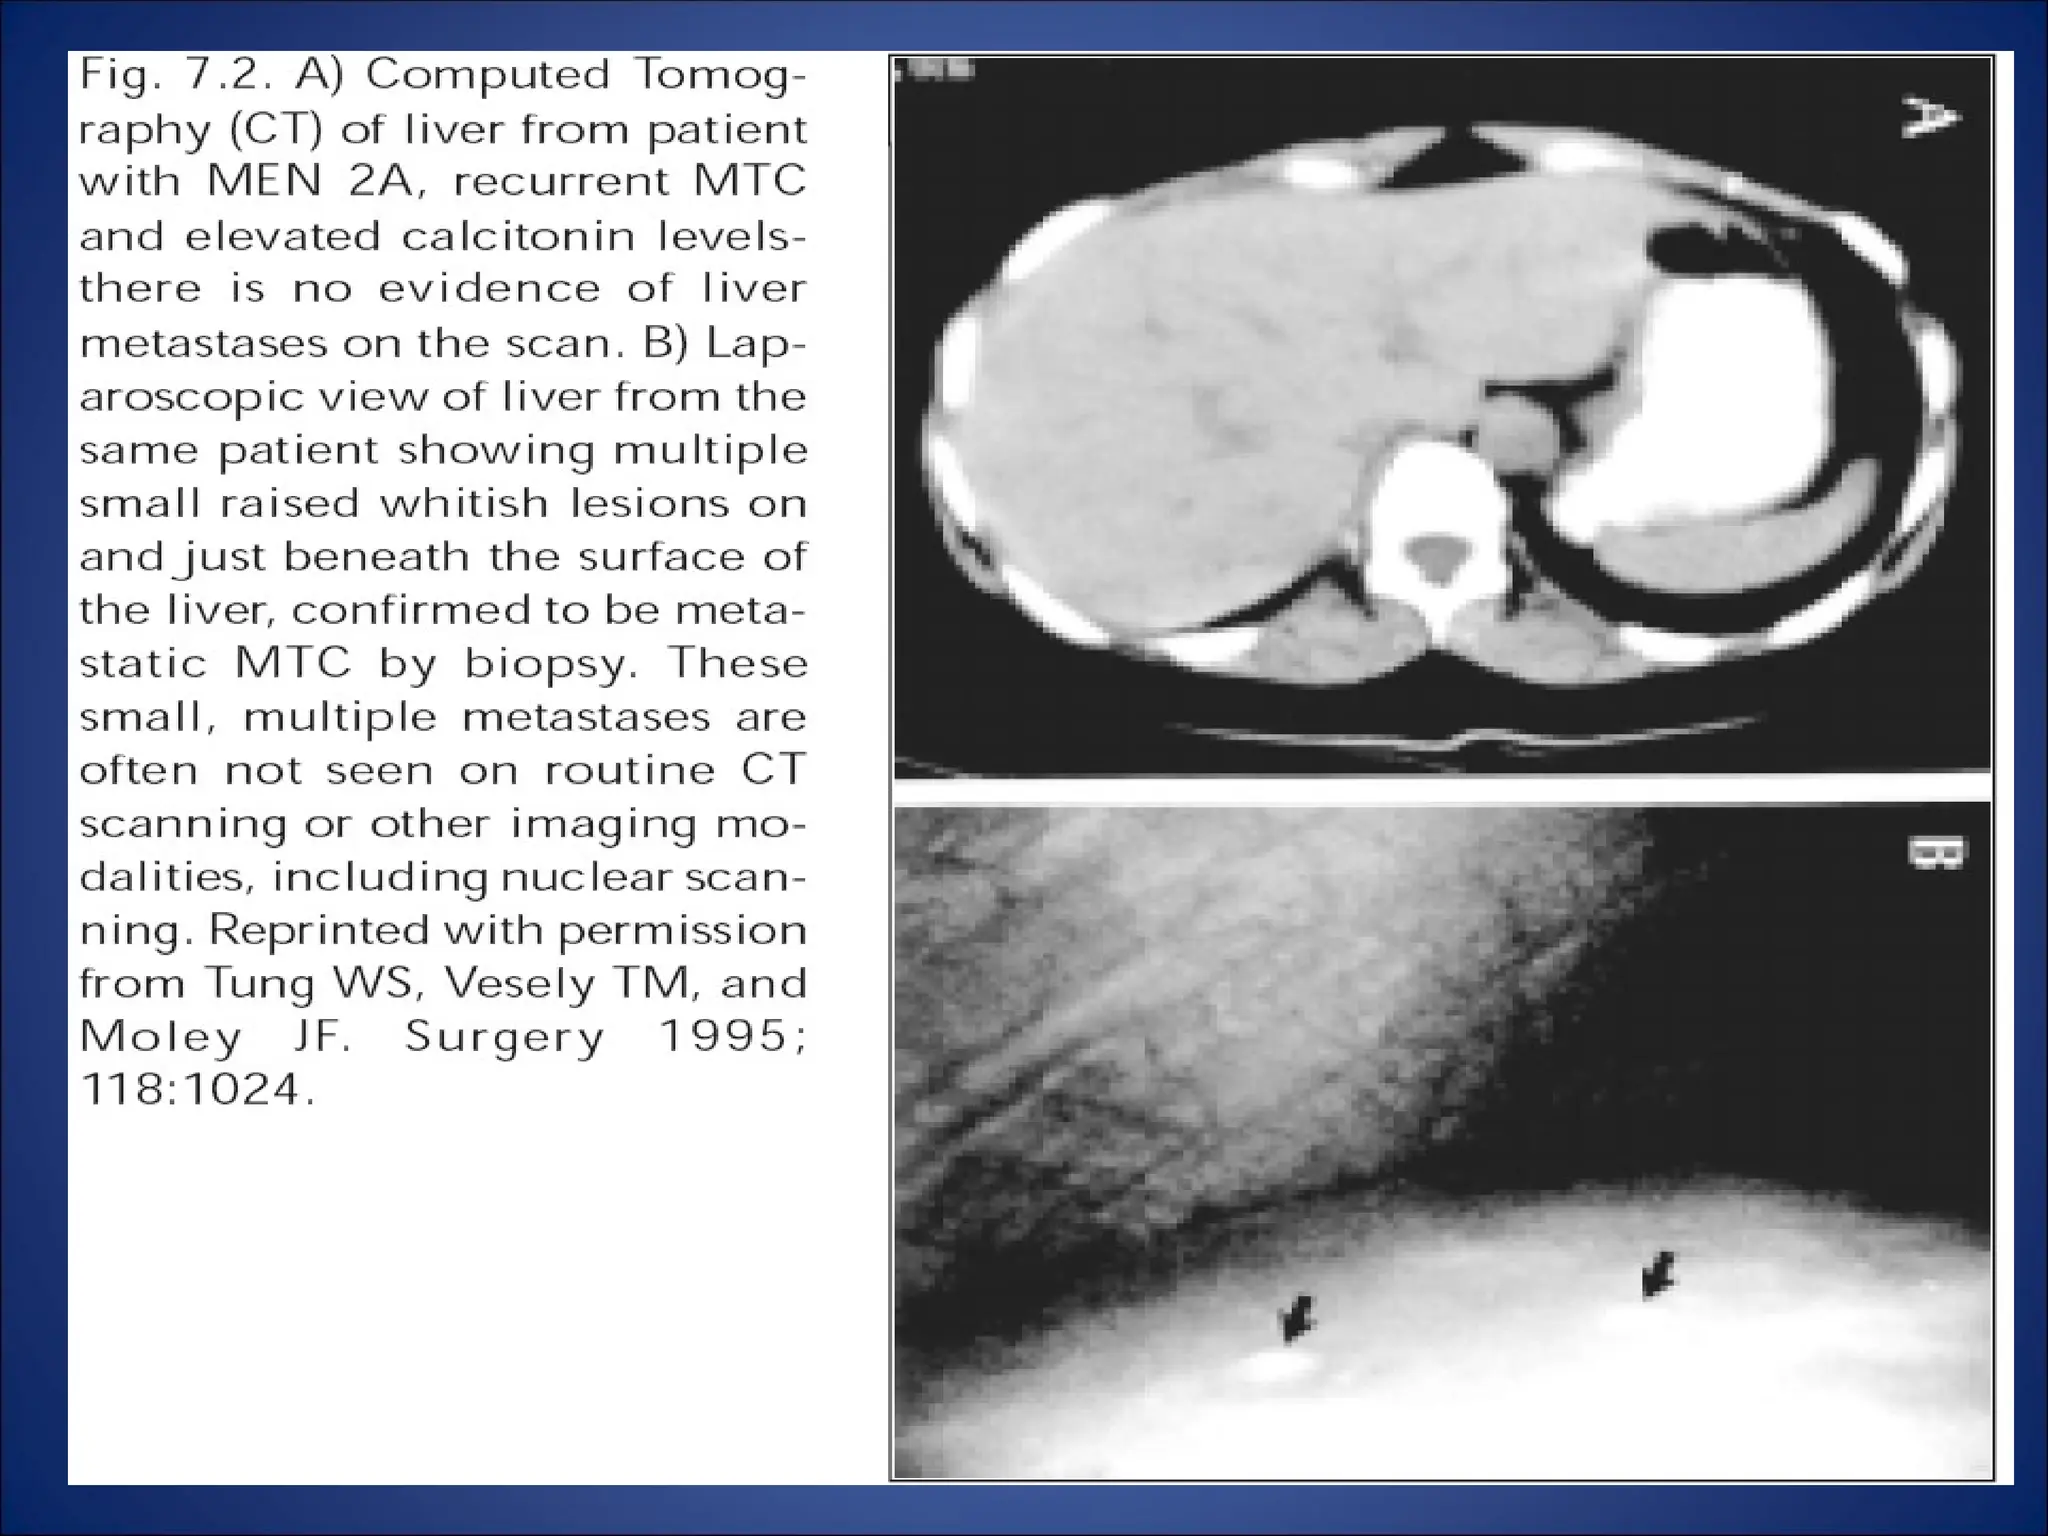

• Liver metastases (>1.5 cm):laprascopic radio

frequency ablation.